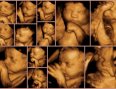

4D ultrazvuk predstavlja najsavremeniji način pregleda trudnica, gde se ultrazvučni talasi softverskim putem pretvaraju u sliku fetusa, koja je izuzetno jasna i fascinantna roditeljima koji sve vreme mogu da posmatraju svoju još nerođenu bebu. Na ovaj način veza između roditelja i bebe postaje još jača.

4D ultrazvuk ima i četvrtu dimenziju-vreme i na taj način se dobija prikaz pokreta fetusa u realnom vremenu. Kada je u pitanju kasnija faza trudnoće, mogu se, pored pokreta i celokupne anatomije u sklopu video snimka uočiti i istezanje, češkanje, sisanje prstića, mrštenje, osmeh fetusa.